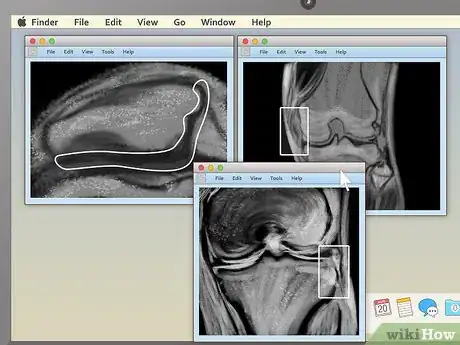

4. 4

Use the section-cut line to see where cross-sections are located. If you display a cross-sectional image along with a sagittal or coronal image, you may see a section-cut line on the second image. This will be a straight line running through the image, but it may not be present on all MRIs. If your image does have one, this shows where on the second image the cross section is located. You should be able to move the section cut line toward the center, right or left of the image. This will change the larger layout image to show the body from the new direction of the scan.

• The section-cut line on the layout picture also shows the direction that the image was taken from. For example, if your MRI were a picture of an everyday object, like a tree, the section cut line might show you if the picture was taken from above in a plane, from a second-story window, or from the ground.

5. 5

Drag the section-cut line to view new parts of the study. Dragging the section-cut line to a different part of the image allows you to "move around" your MRI images. The image should change your view to the new area automatically.

• For example, if you're viewing a sagittal image of your spine along with a cross section of one of your vertebrae, moving the section-cut line may allow you to cycle up and down through the various vertebrae above and below it. This can be useful for locating problems like herniated discs.